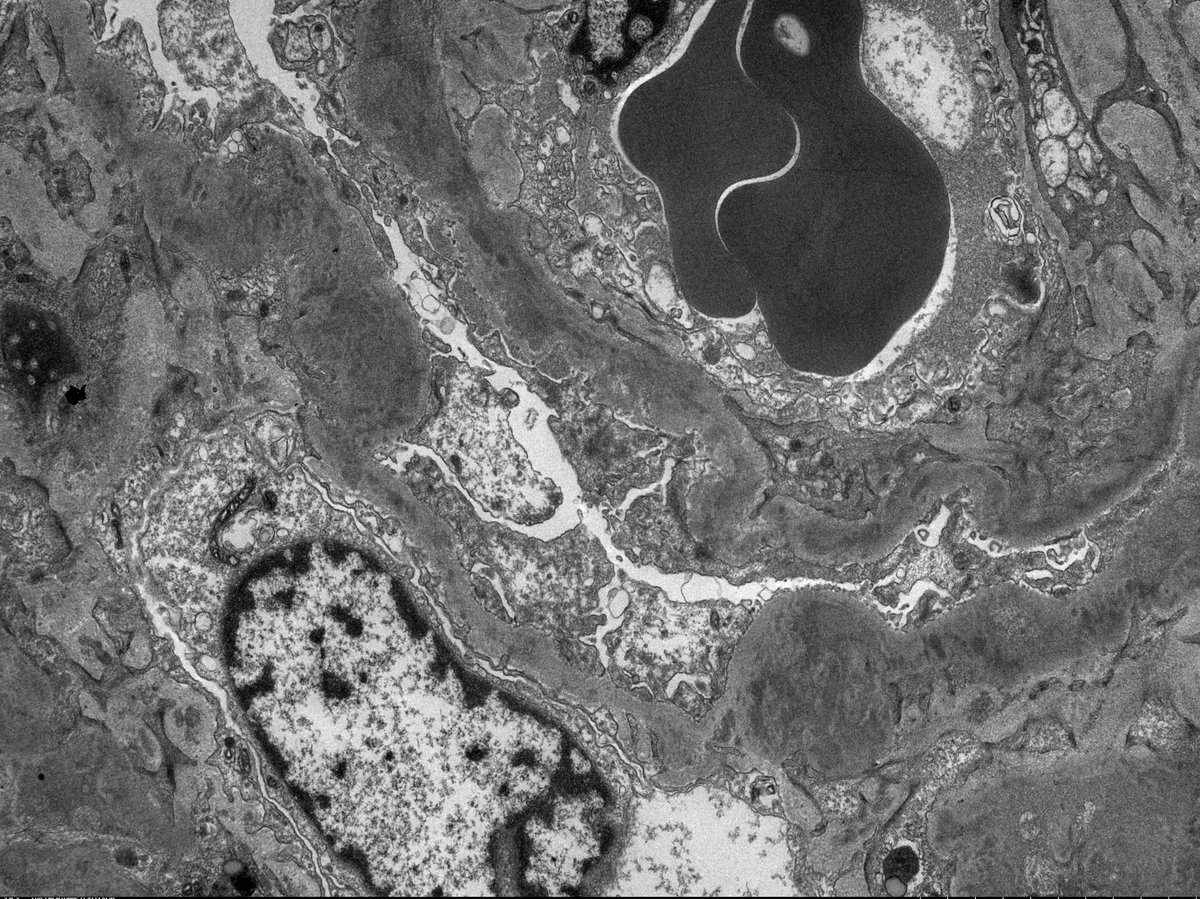

C3 GN in 11 yo boy with proteinuria, hypertension, low C3 (normal C4). EM shows irregular thickening of glomerular capillary wall and mesangial expansion by electron dense deposits. The deposits are somewhat ill-defined with early sign of resorption.